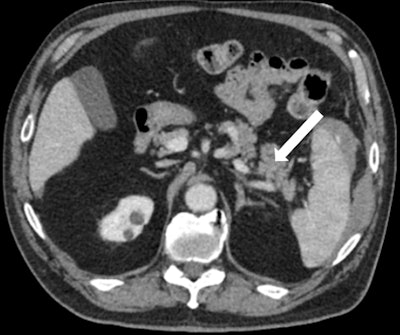

After initial resuscitation and focused assessment with sonography in trauma (FAST), he underwent a CT of the chest, abdomen, and pelvis that revealed a 1.4-cm grade III splenic laceration near the anterior lip associated with a focus of contrast extravasation. The exam also revealed an associated subcapsular hematoma larger than 50% of the surface area of the spleen, with hemorrhage tracking along the left paracolic gutter into the pelvis (figures 1A and 1B). The pancreas appeared unremarkable on this CT (figure 2).

Figures 1A and 1B: Axial and frontal views of CT of the abdomen with IV contrast show a focus of active extravasation within the spleen (above) associated with a large subcapsular hematoma (below). All images courtesy of Dr. Shruthi Suresh et al.